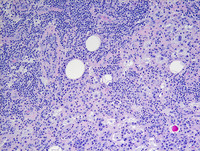

Figure 4: Breast lump-IgG4

Low power (Image to the left) and high power (Image to the right) photomicrographs showing increased IgG4 positive plasma cells, which are often seen in RDD but does not mandate designation as IgG4 related disease.